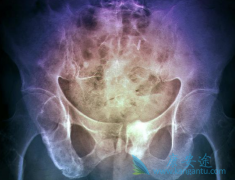

骨髓瘤能活多久 ?有个案例是70岁的李老太由于反复出现骨折只能入院治疗。谁知在治疗时,又被查出患有多发性骨髓瘤,这结果让李老太和她的家人都感到震惊。其实这样的事情很常见。中老年人常出现的问题骨头痛、骨折、多尿……不一定就是缺钙或者是身体 ...

• 什么是多发骨髓瘤?如何看多发骨髓瘤的严重程度

多发骨髓瘤 单看疾病的命名,大多数患者会自然的认为是“实体瘤”。其实并不是这样,这个主要是指骨髓内的造血细胞异常,这种细胞叫做浆细胞,是白细胞的一种。也就是产生人体抗体免疫球蛋白的细胞。要看多发骨髓瘤严重程度,比较直接是看原始浆细胞比 ...

• 如何识破那些引起骨髓瘤症状的错误诊治

骨髓瘤患者的临床表现往往是身体多器官,多部位的,同时,由于人们对这个病认识不充足,导致对某些常见 骨髓瘤症状 表现,比如腰酸背痛,关节疼痛,感染现象等,常常出现误诊误治的现象,最终可能会延误治疗时机,影响预后。   如何识破那些引起骨髓瘤 ...